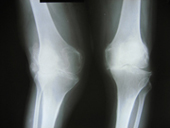

Arthritis both knees varus deformity pre op Post op Total Knee Replacement Post op Total Knee Replacement

Total knee replacement relieves pain and limp, corrects deformity and helps the patient to walk normally. A new technique “Minimally invasive solutions-Mini Incision Total knee replacement” has been introduced recently. The advantages of mini incision TKR are as follows,

• smaller incision

• speedy recovery

• reduced post op pain

• reduced blood loss

Zimmer Institute, USA, has a satellite center in Bangkok. Dr. Alphonse Mariadoss went to this center at their invitation to attend a course and gained good expertise in MIS Mini incision Total hip and knee joint replacements.